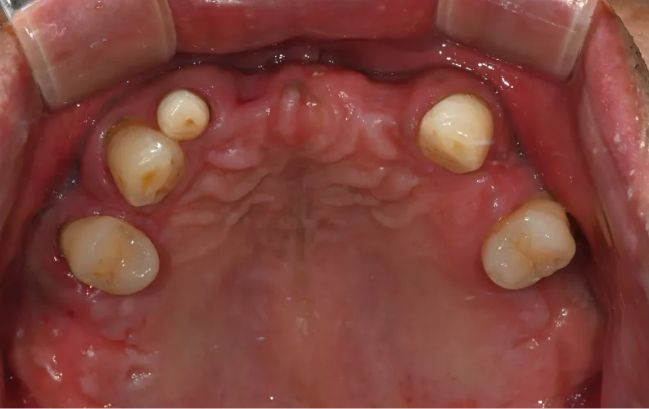

2022-02-03

2022-06-0750대 남성, 원데이 수면 전체 임플란트 19개 식립